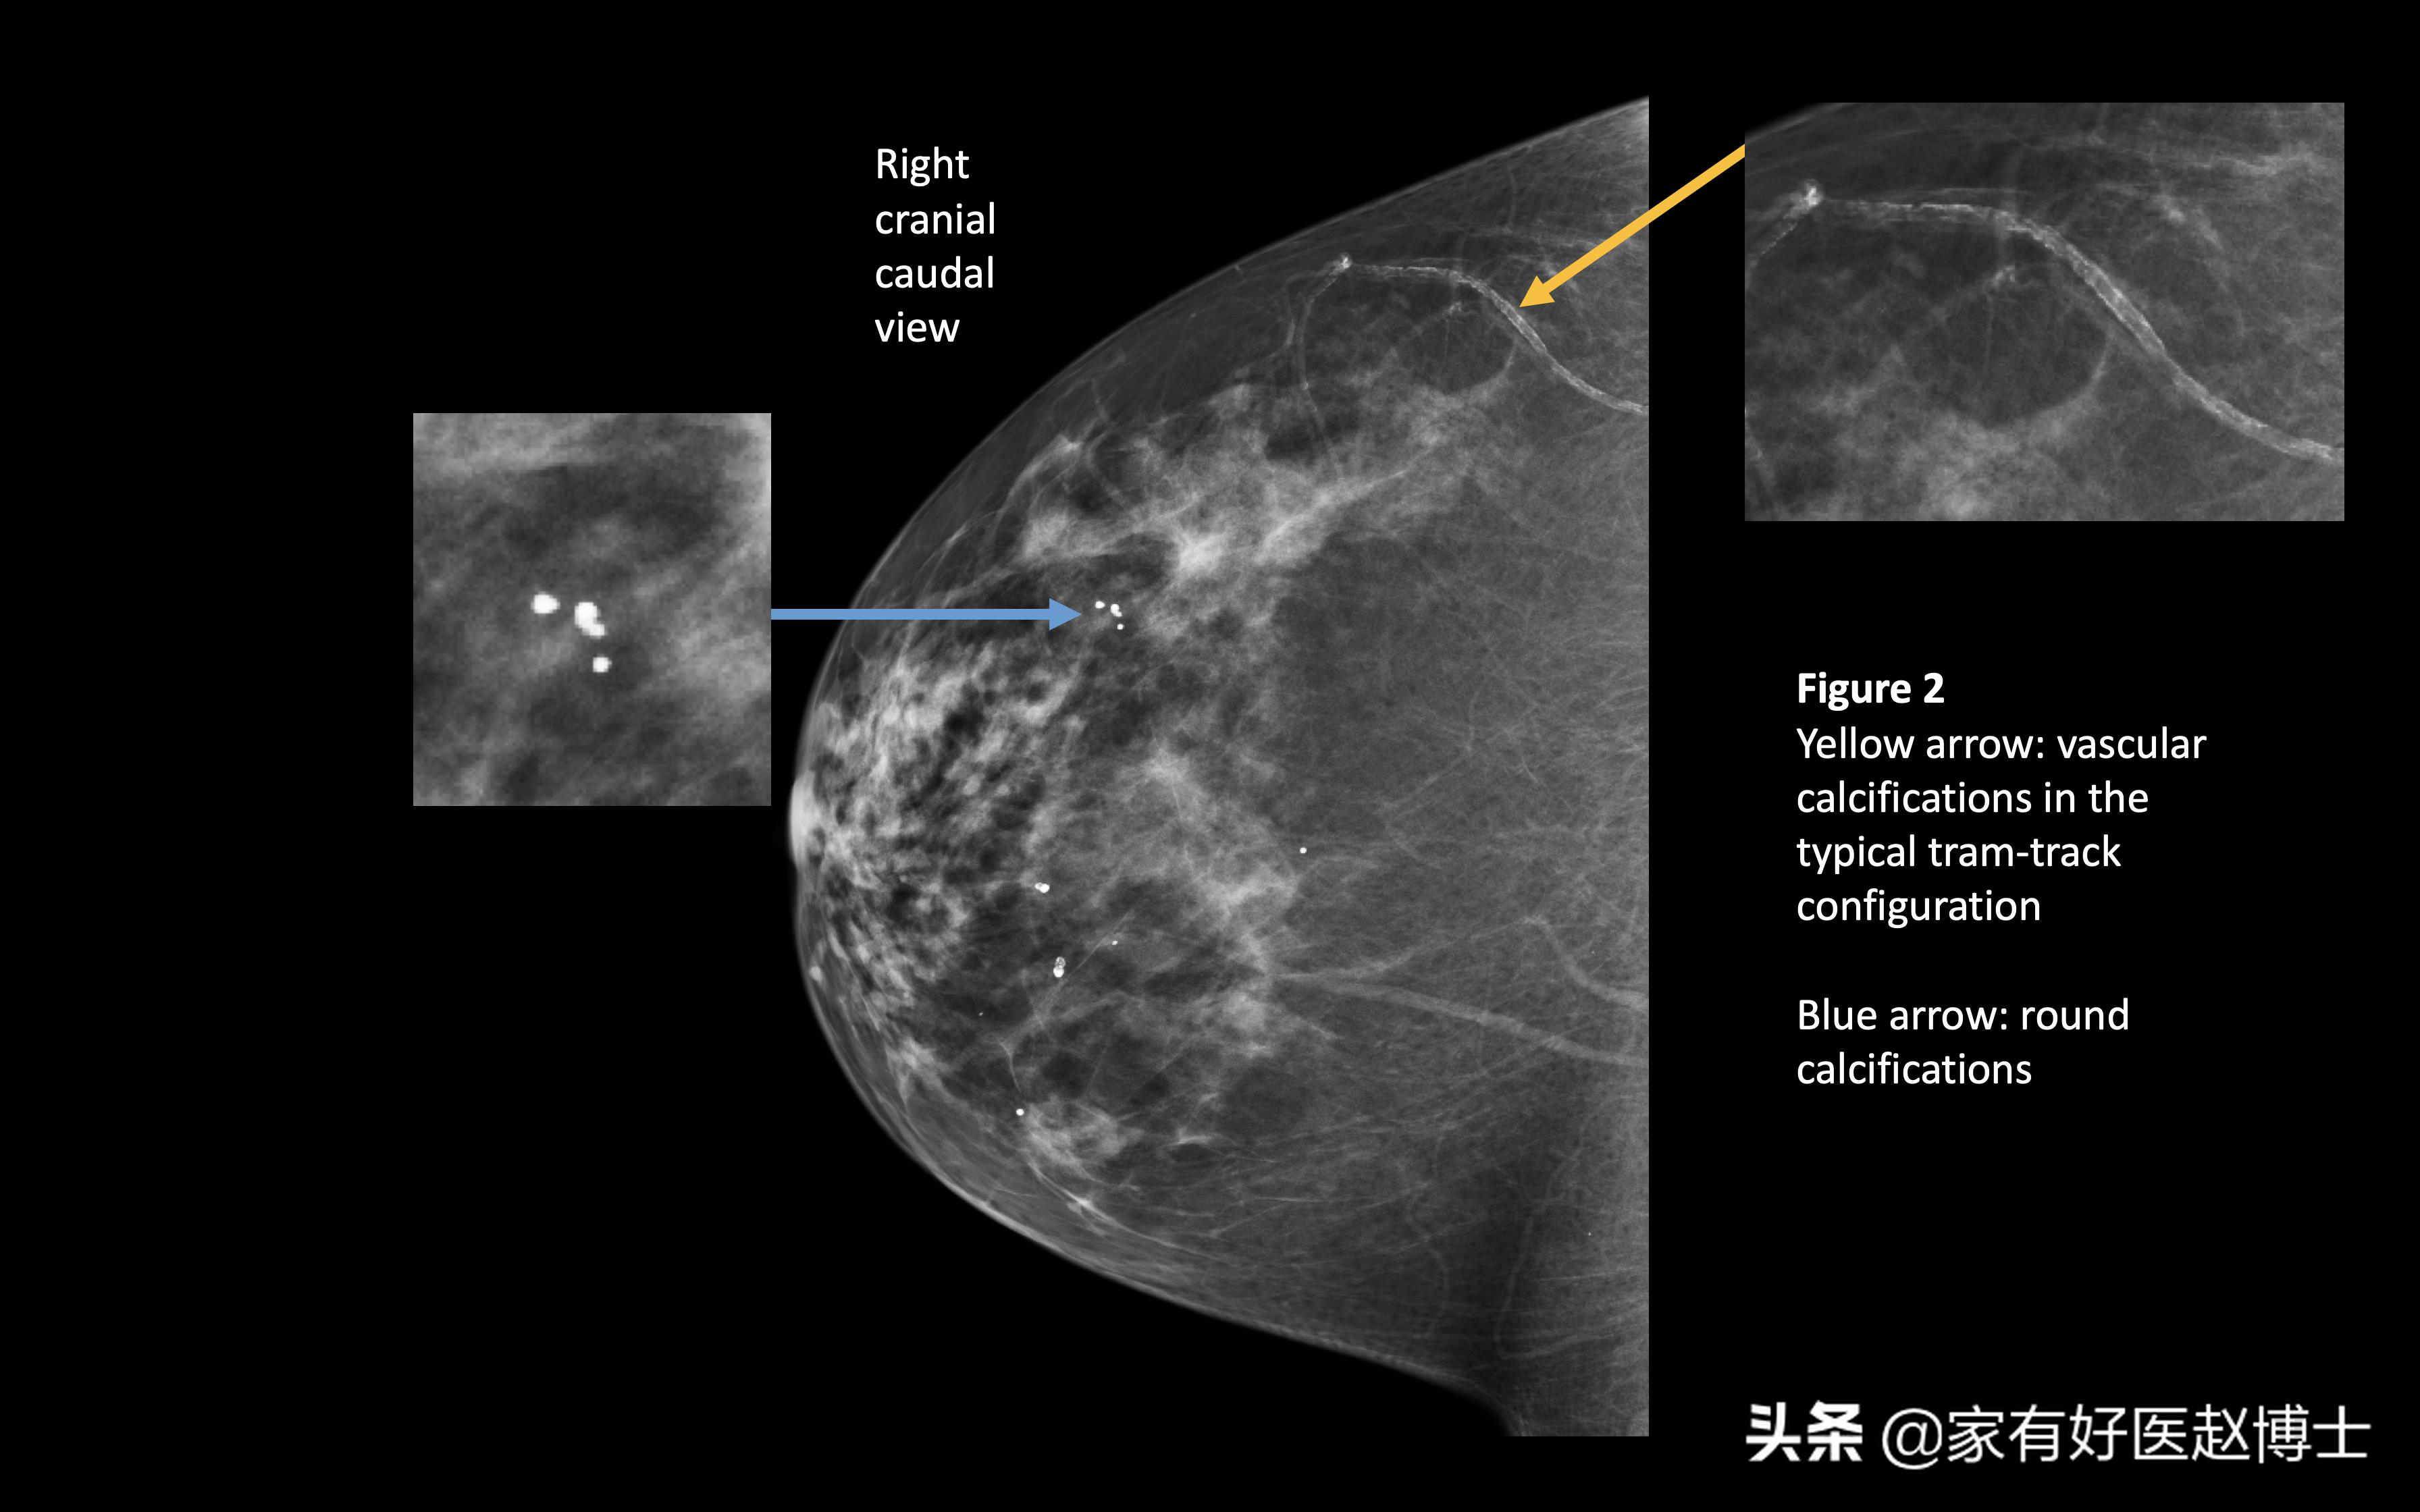

第二个要说的存在恶性风险的是乳腺钙化。目前,对乳腺钙化尤其是微小钙化,识别能力最强的检查方法是乳腺X线摄影,而不是乳腺超声。

所以,大家不要觉得体检做了乳腺超声就可以了,对于年龄超过40岁、乳腺癌风险较高的女性,最好是能够把乳腺X线摄影和乳腺超声都做一下,这样才不容易漏掉一些早期的乳腺癌征象。

乳腺的钙化征象是存在良恶性之分的,一般认为,分散的、粗大的乳腺钙化往往提示良性概率大,可能是乳腺增生、乳腺炎或乳腺导管扩张等病因引起的;而当乳腺中发现密集的、细小的钙化灶,尤其是单位面积内存在多于7~8个钙化点时,需要高度警惕乳腺癌的风险。